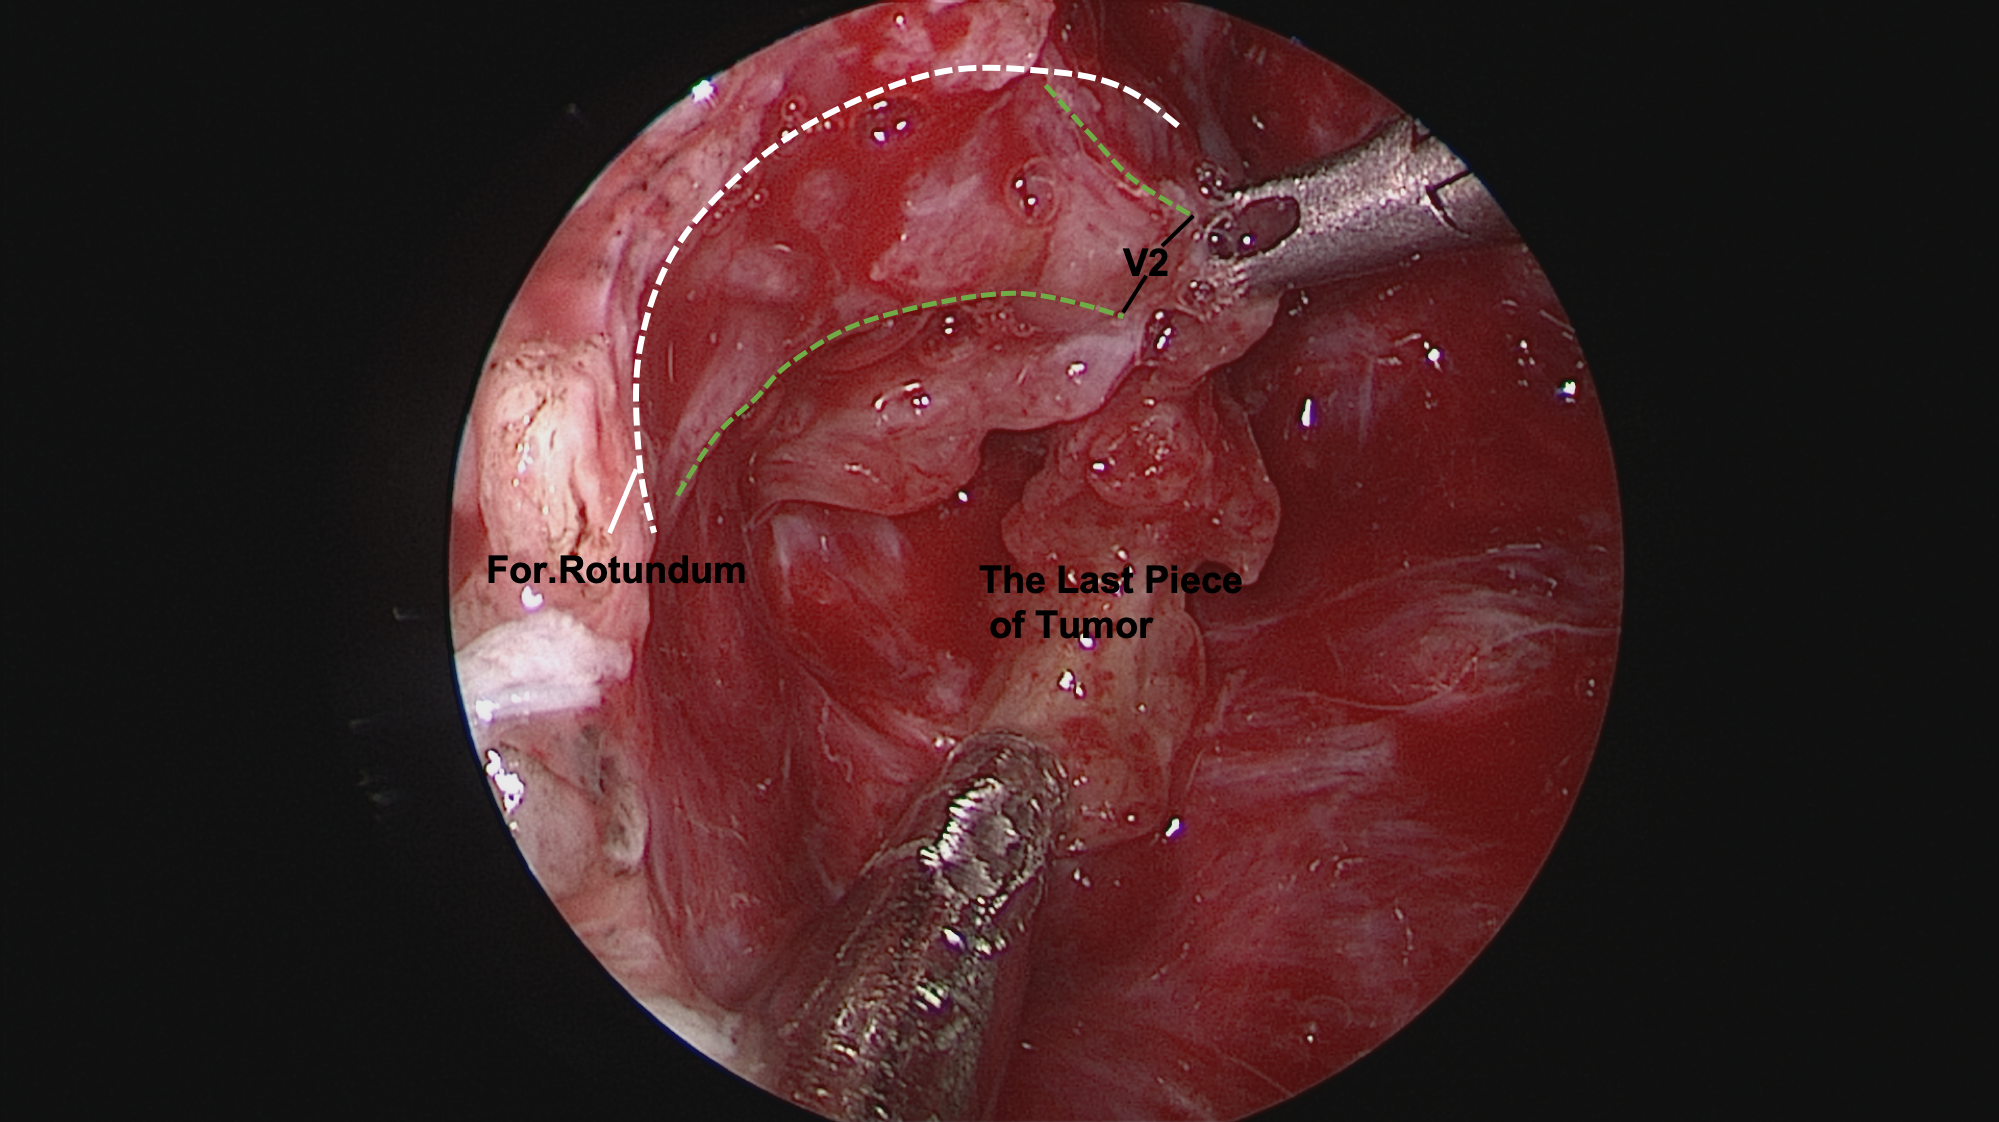

图9.暴露翼腭窝中肿瘤,切开肿瘤包膜后,从肿瘤前方、内侧方给予瘤内分块切除肿瘤。

图10.肿瘤起源于中颅底圆孔,圆孔已明显扩大

图11.肿瘤完全切除